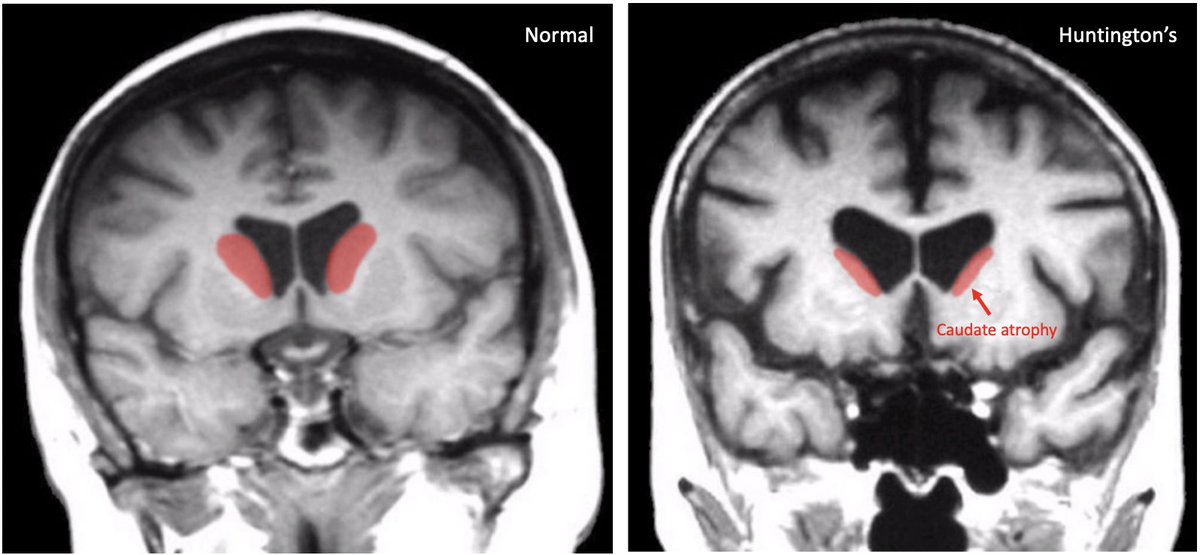

๐ฅ๐ฎ๐ฑ๐ถ๐ผ๐น๐ผ๐ด๐ of Huntington's:

โ not typically used for diagnosis

โ striatal atrophy may be evident on MRI years prior to clinically diagnosable HD

๐๐ง/๐ ๐ฅ๐: caudate atrophy & enlarged frontal horns of lateral ventricles

๐ฃ๐๐ง: hypometabolism in basal ganglia